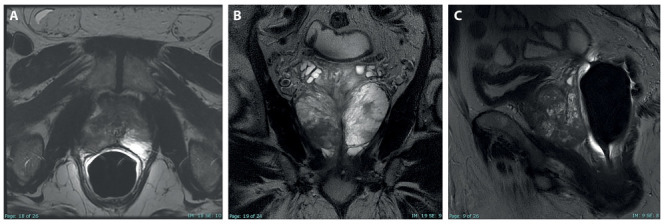

我们报告了一例63岁的男性患者,他来到泌尿外科诊所,前列腺特异性抗原值增加,直肠指检时不对称增大。该男子接受了前列腺MRI检查,随后对前列腺癌症进行了令人信服的放射学诊断。患者被指定为T3a N0疾病的临时阶段。为了证实这一诊断,进行了前列腺活检,但组织学分析报告了非特异性肉芽肿性前列腺炎(GP)。TRUS和MRI在临床和放射学上通常模拟前列腺癌症(PCa),这是一种罕见的情况,由于其非特异性症状和特定的放射学发现,这是诊断挑战。在本病例报告中,我们讨论了这种罕见临床疾病的磁共振成像特征,以帮助放射科医生及时诊断,获得正确的诊断框架。

We report the case of a 63-year-old male who came to the urology clinic with an increasing value of the prostate specific antigen and an asymmetrical enlargement at the digital rectal examination. The man was subjected to an MRI of the prostate following which a convincing radiological diagnosis of prostate cancer was made. The patient was assigned a provisional stage of disease T3a N0. In order to confirm this diagnosis, a prostate biopsy was performed but the histological analysis reported non-specific granulomatous prostatitis (GP). It is an uncommon condition that both clinically and radiologically on TRUS and MRI usually mimics prostate cancer (PCa), representing a diagnostic challenge due to its non-specific symptoms and aspecific radiological findings. In this case report we discuss the magnetic resonance imaging features of this rare clinical condition in order to help radiologists in the timely diagnosis for a correct diagnostic framing.